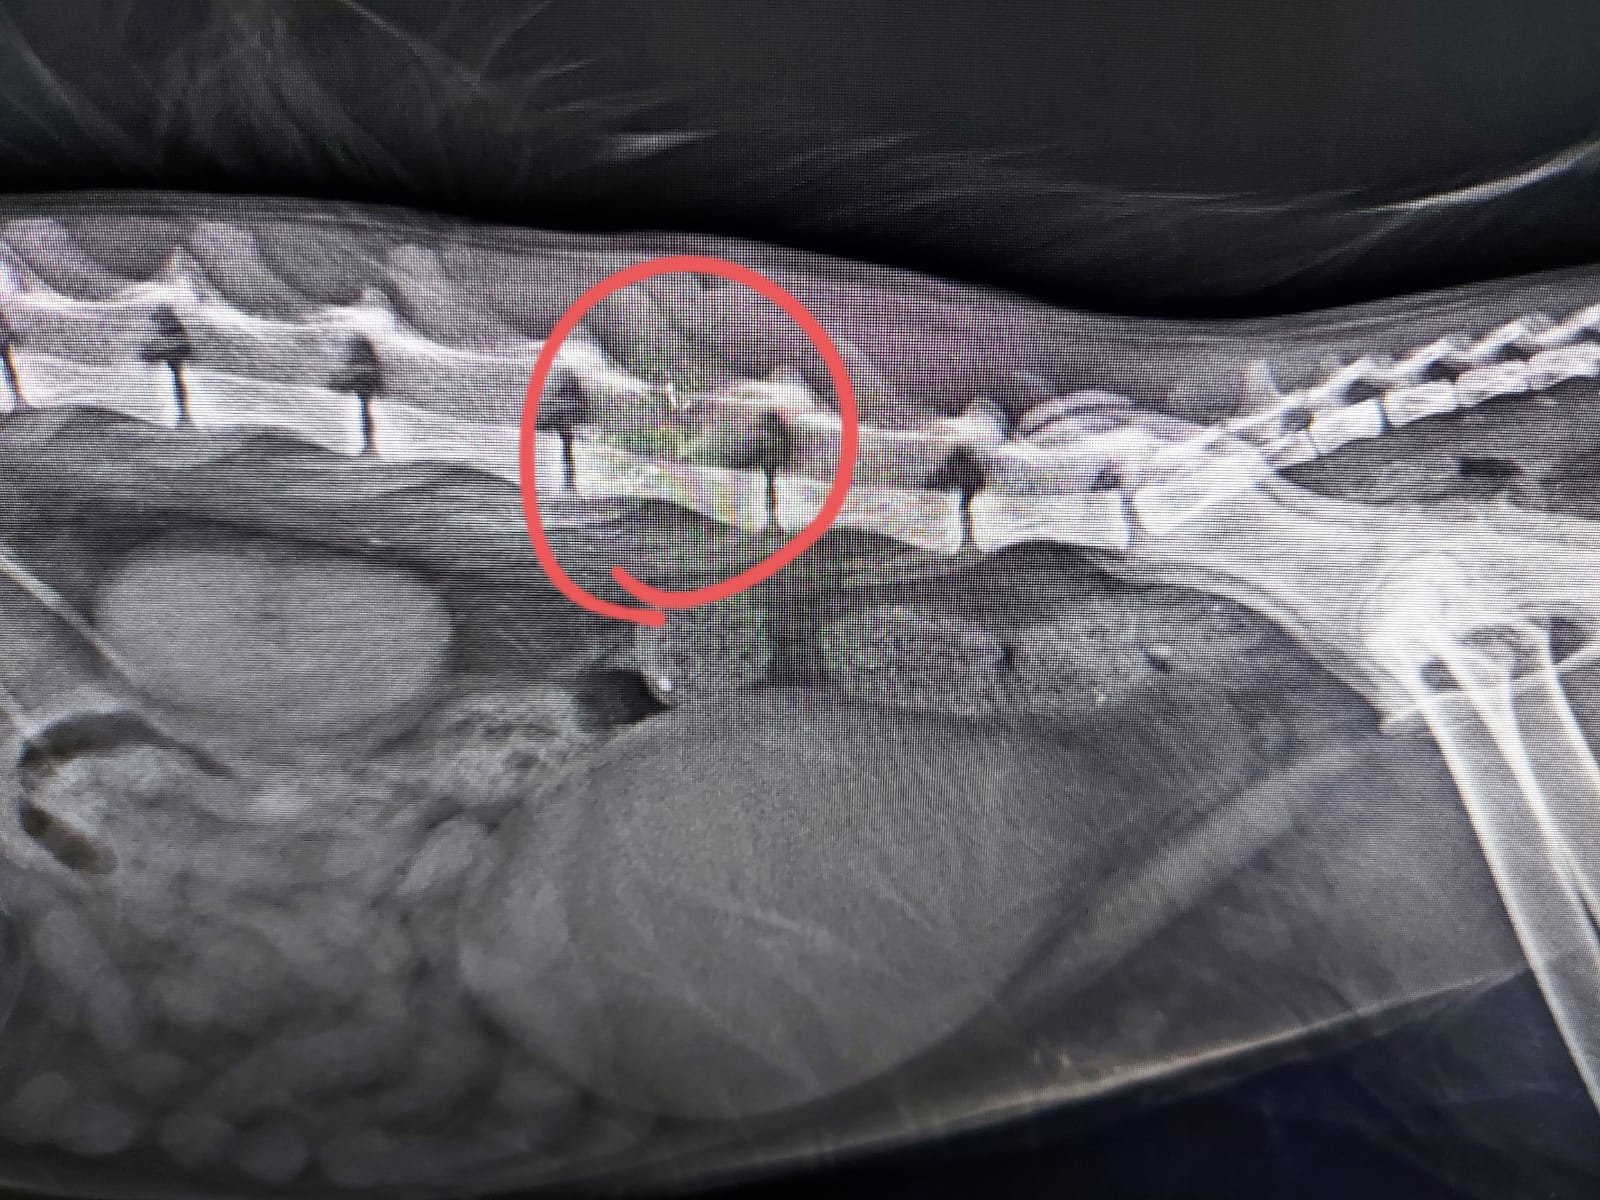

Nazilli’de arka ayaklarını kullanamadığı düşünülen kedinin havalı tüfekle vurulduğu ve sağ bacağının uyluk kemiğinde saçma olduğu ortaya çıktı.

GÜNAY PABUŞÇU- Veteriner hekim Mehmet Gün ve Özhan Angın, saçmanın omurgayı parçaladığını ve vücutta yol aldığını tespit ettiklerini açıkladı.

Görüntüleri inceleyen Gün, kedinin sağ bacağının uyluk kemiğindeki kaslara geçmiş şekilde bir kurşun olduğunu gördü. Saçmanın bulunduğu konumun kedinin yürümesine engel olmadığını saptayan Gün, gerçeği operasyonda öğrendi.

Gün, “Röntgenlerde 5. lumbal omurda bir hasar olduğunu tespit ettik ve kedinin bu omura çok yakın bir yerden yaralandığını gördük. Operasyondan önce ilgili alanları traş edince, havalı tüfeğe ait kurşunun vücuda sol taraftan girdiğini, omurgayı parçaladığını ve sağ taraftaki kas dokusuna doğru ilerlediğini gördük. Bunu da kedinin doğal hareketlerine bağladık.” diye konuştu.